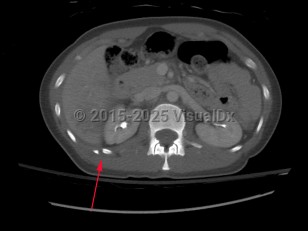

Causes / typical injury mechanism: Rib fractures are a common injury of the thoracic cage. They may be traumatic or pathologic. Depending on the location and the number of ribs involved, be alert for possible visceral injuries, pulmonary contusions, pneumothorax, or vascular injury.

Fractures of the lower ribs (9-12) could indicate concomitant intraabdominal injury.